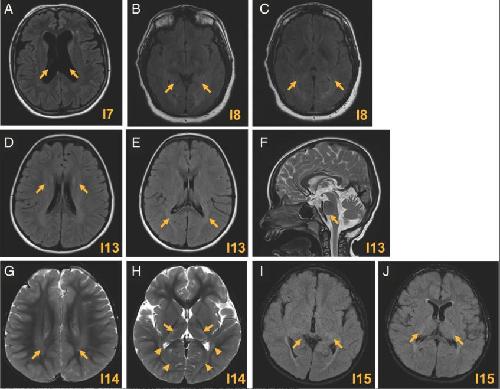

HCN2-Associated Neurodevelopmental Disorders: Data from Patients and Xenopus Cell Models., Houdayer C,Phillips AM,Chabbert M,Bourreau J,Maroofian R,Houlden H,Richards K,Saadi NW,Dad'ová E,Van Bogaert P,Rupin M,Keren B,Charles P,Smol T,Riquet A,Pais L,O'Donnell-Luria A,VanNoy GE,Bayat A,Møller RS,Olofsson K,Jamra RA,Syrbe S,Dasouki M,Seaver LH,Sullivan JA,Shashi V,Alkuraya FS,Poss AF,Spence JE,Schnur RE,Forster IC,Mckenzie CE,Simons C,Wang M,Snell P,Kothur K,Buckley M,Roscioli T,Elserafy N,Dauriat B,Procaccio V,Henrion D,Lenaers G,Colin E,Verbeek NE,Van Gassen KL,Legendre C,Bonneau D,Reid CA,Howell KB,Ziegler A,Legros C, Ann Neurol. September 5, 2025; 98(3):1531-8249.